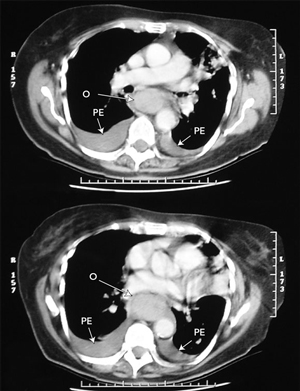

Computed tomography was arranged to investigate the oesophageal symptoms. This showed a diffusely thickened oesophagus from the thoracic inlet to the gastro-oesophageal junction, bilateral pleural effusions, and left lower lobe collapse and consolidation (Figure). Endoscopy showed blackened oesophageal mucosa with extensive mucosal bleeding. The procedure was abandoned because of these findings, and the patient was intubated and transferred to our tertiary referral centre for ongoing care.

Dissecting haematoma of the oesophagus has a typical appearance on imaging.4,5 Barium swallow shows a long, smooth tubular filling defect in the lumen of the oesophagus, sometimes with the dissection space filled with a stripe of contrast (the “double-barrelled oesophagus”). As the dissection most commonly occurs along the posterior wall, the lateral view is most useful. Computed tomography demonstrates an obliterated lumen with thickening of the wall. This extends over a long length of the oesophagus, and can mimic oesophageal rupture or extensive malignancy. The haematoma is large, fluctuant, and blue or purplish when viewed at endoscopy. Delayed endoscopy shows a long ulcer, where the overlying mucosa has sloughed, followed by rapid regeneration and an ultimately normal appearance.3